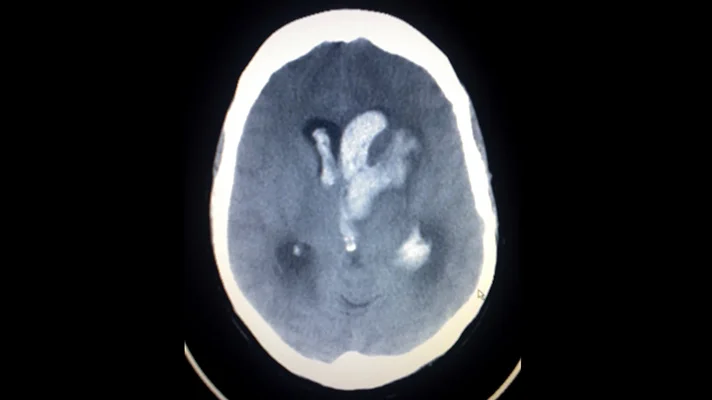

Detecting brain bleeds

IBM Watson Health and Israel-based MedyMatch Technology are joining their AI forces in hospital emergency rooms to help doctors detect intracranial bleeding resulting from head trauma and stroke. The MedyMatch algorithm uses deep learning, machine vision, patient data and clinical insights to automatically highlight for a physician areas that might indicate the potential presence of cerebral bleeds.